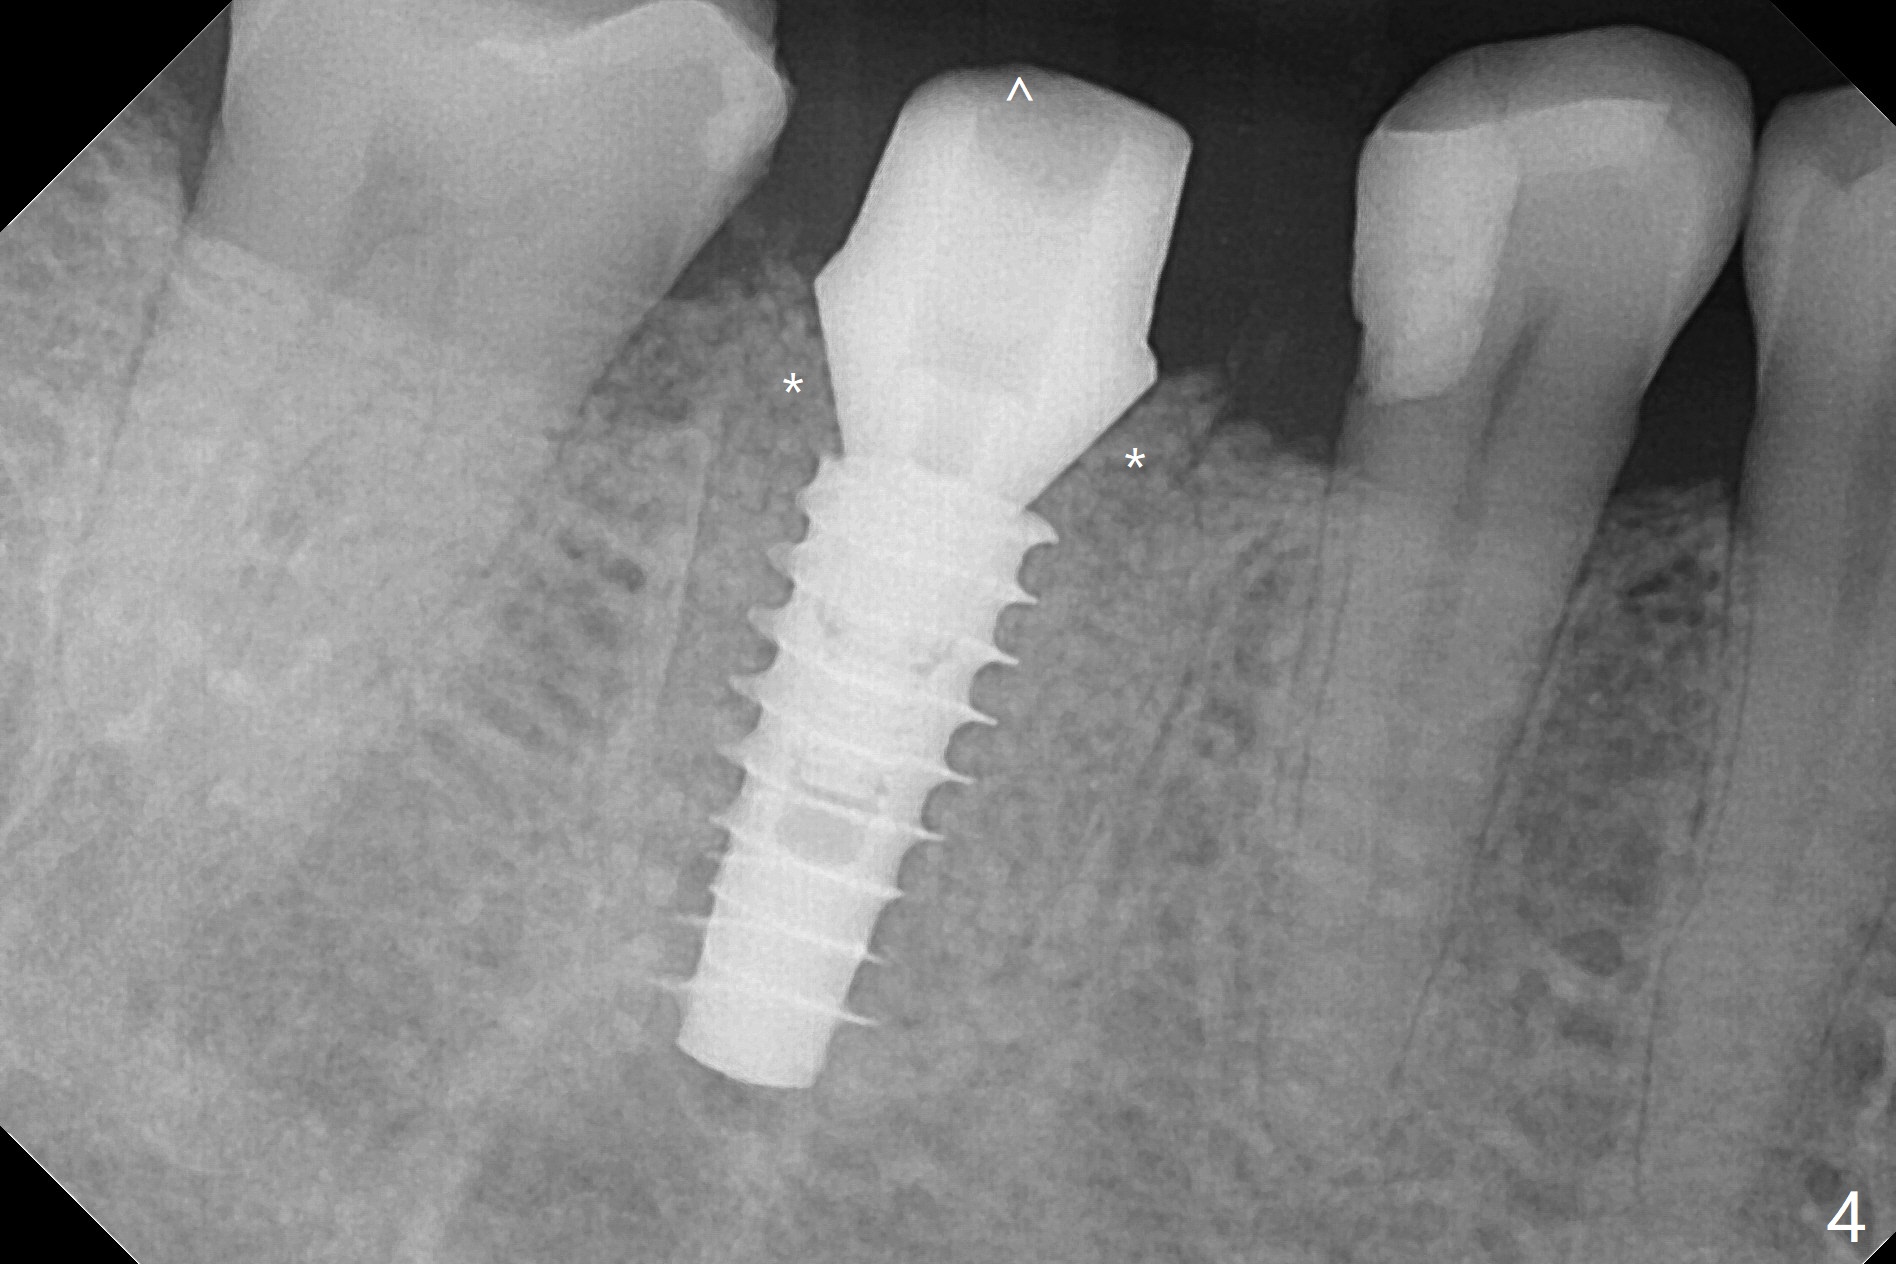

牙冠断裂,好像容易保留牙根,其实还挺多工作。使用12毫米平磨钻头后,中隔中央形成凹陷,不过使用2.2x7.3毫米钻头后,钻洞开始偏移远中(图一)。完成3.5x11.5毫米钻洞,4x10毫米报废植体扭力很高(图二)。为了植入5x11毫米植体(扭力35Ncm),必须使用4.5x11.5毫米钻头(图三)。虽然根尖骨质不多,稳定性部分来自残余颊侧,舌侧中隔。即刻放置的基台远中舌侧必须大量磨去(图四:^)才有足够空间做临时牙冠,说明牙冠会折裂病人咬合力大。保留牙根工作量大,仍有偏差(与图五(设计)相比),仿佛好处不大,以后少做。由于临时牙冠舌侧做的大些,术后八天取出修正,伤口愈合正常(图六)。术后一个月一部分骨粉好像被转化为牙龈(图七)。术后3.5月病人抱怨咀嚼疼痛,植体松动,放置愈合基台。一个月后植体仍松动,疼痛(图八)。术后6.5月,植体不再松动,放置修复基台(图九),取模。